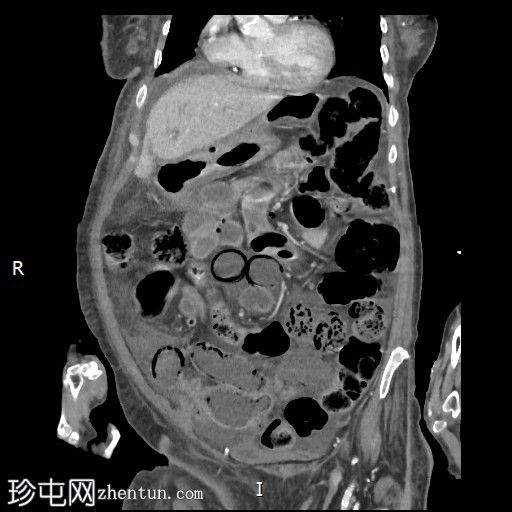

X线检查

多处小肠袢扩张。

结肠内可见少量粪便。